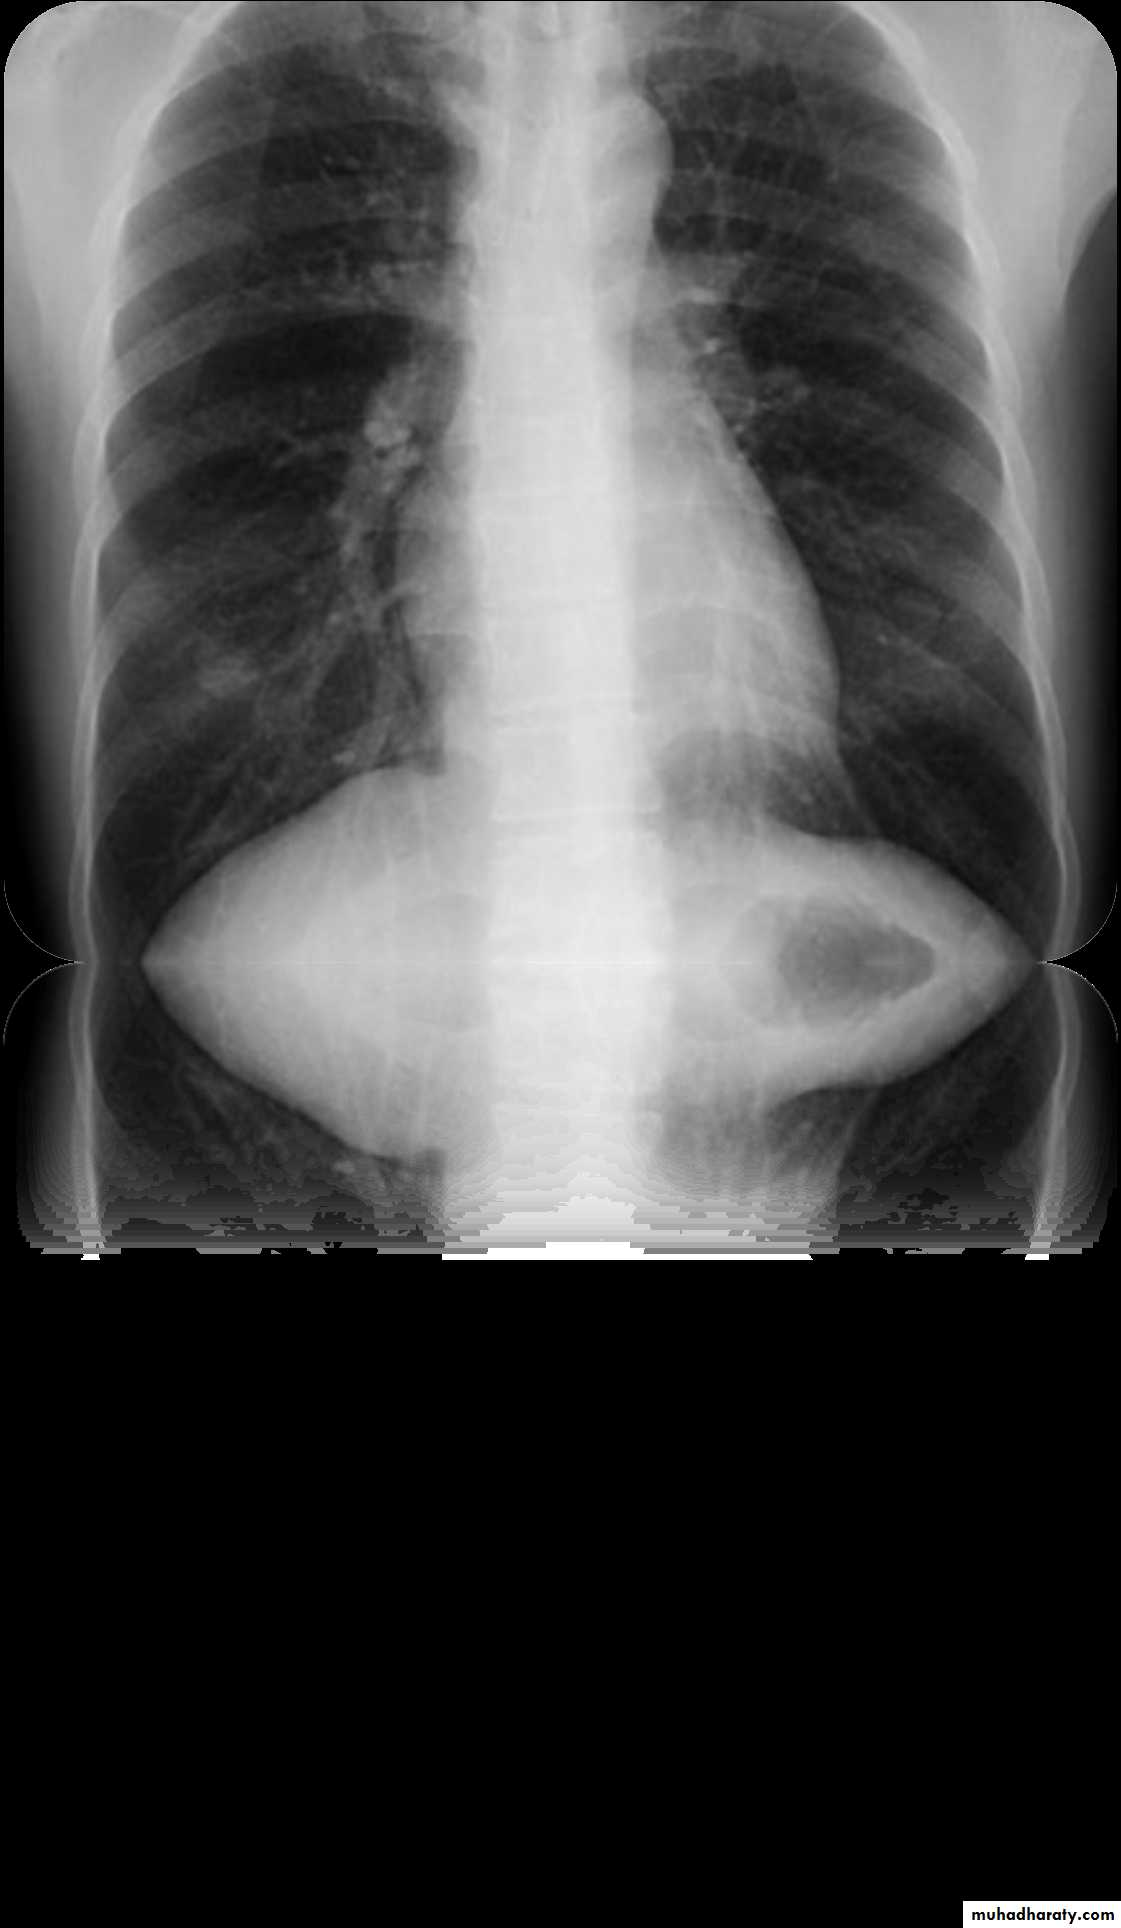

Pleura effusion signs

Obliteration of costo-pherinic anglesMeniscus sign

Lenticular sign

A subpulmonic effusion

(infrapulmonary effusion) accumulation of fluids between the lung & visceral pleura ..The following features are helpful :elevation of the hemidiaphragm ..right: peak of the hemidiaphragm is shifted laterally

left: increased distance between lower lobe air and gastric air bubble